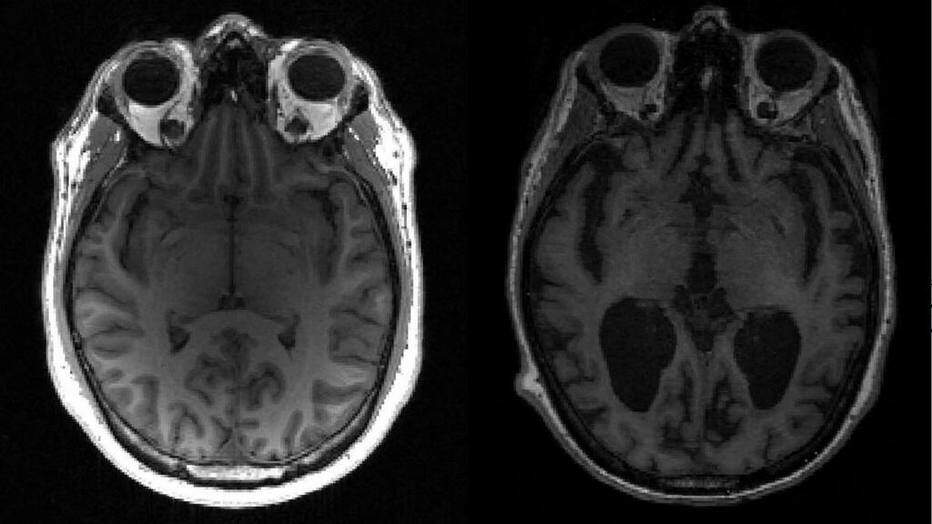

Os pesquisadores também descobriram que os pacientes com covid eram 80% mais propensos a desenvolver problemas cognitivos como “névoa cerebral”, confusão mental e esquecimento. Eles ainda tinham uma propensão 34% maior de desenvolver distúrbios por uso de opióides e 20% mais propensos a desenvolver distúrbios por uso de substâncias não opióides, incluindo alcoolismo.